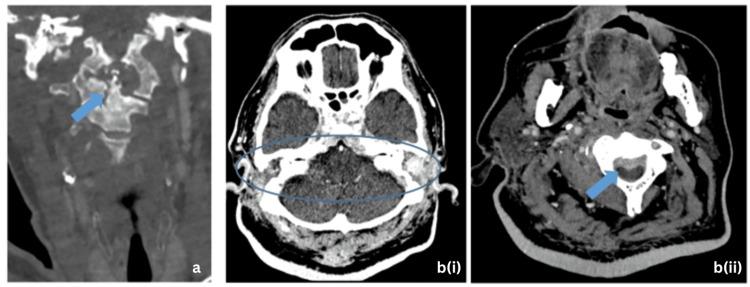

Abstract

Skull base osteomyelitis is a not commonly encountered but potentially fatal consequence of untreated necrotizing otitis externa. Early recognition and appropriate treatment are crucial to prevent serious complications such as cranial nerve palsies, meningitis, and intracranial abscess formation. The case reports presented in this study provide a rich depiction of the clinical presentation, diagnostic challenges, and interventions employed. Early recognition and appropriate management of skull base osteomyelitis are crucial to prevent complications and improve patient outcomes.